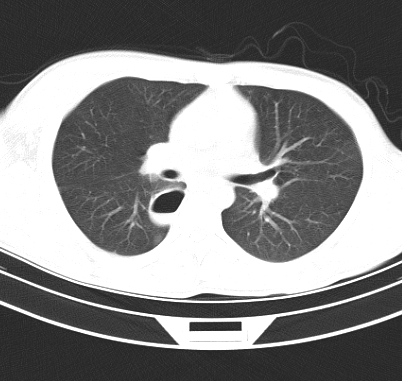

标题: CT19170:男 24岁,胸部外伤一周行CT检查 [打印本页]

男 24岁,胸部外伤一周行ct检查 未传纵隔窗

考虑----右肺下叶背段包裹性液气胸

右肺下叶背段包裹性液气胸。

首先考虑肺裂伤形成的液气囊肿.纵膈胸膜包裹性的液气胸可能性小,病变主要在肺内.

壁光滑完整,周围未见炎性灶及粘连带,考虑肺囊肿,不一定跟外伤有关!

有否先天性可能,病程仅一周,病灶周围实质无明显异常表现.

右肺下叶纵隔胸膜下液气囊肿,考虑肺囊肿?肺隔离症?